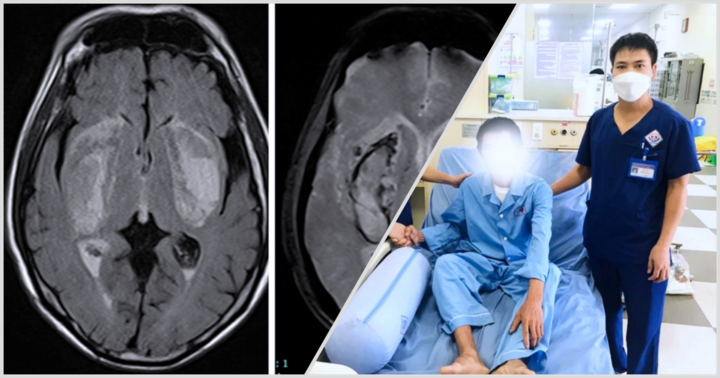

Người đàn ông 63 tuổi bị ngộ độc methanol nặng, đe dọa tính mạng sau khi uống rượu ngâm không rõ nguồn gốc.

Người đàn ông nhập viện cấp cứu trong tình trạng hôn mê sâu, da tím tái, chân tay lạnh và tiểu tiện không tự chủ, được chẩn đoán bị ngộ độc cấp methanol tiên lượng rất nặng.

Kết quả xét nghiệm cho thấy người bệnh bị ngộc độc methanol cấp, mức độ nặng (nồng độ methanol 78,13 mg/dl).